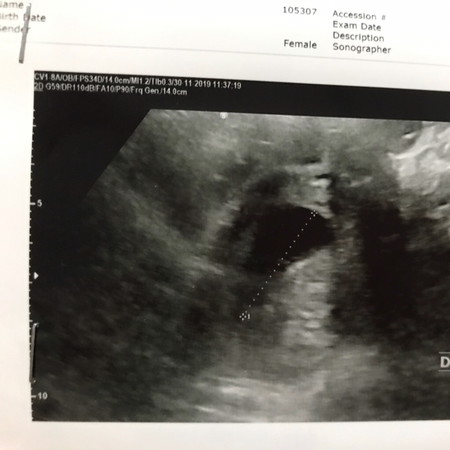

ขออนุญาติรบกวนสอบถาม " เรื่องท้องลม " ค่ะ..... อาจยาวหน่อยนะคะตอนนี้เป็นกังวลและเครียดมากค่ะ ? มีแม่ๆท่านไหนเคยประสบการณ์ท้องลมบ้างคะ มีอาการอย่างไรกันบ้าง เช่น ปวดท้อง , หรือเลือดออกกันไหม . - พอดีของเราท้องได้ 8 สัปดาห์กว่าๆ แต่คุณหมอเจอแต่ถุง ไม่พบตัวอ่อน คุณหมอแจ้งว่าครรภ์อาจผิดปกติหรือเสี่ยงท้องลมได้ เลยรอให้มาซาวน์ใหม่อีก 2 อาทิตย์ คุณหมอท่านก็ใจดีค่ะ ไม่ตัดสินเลยว่าท้องลม ก็ให้ยาบำรุงมาทานปกติ - ส่วนอาการเราเองปกติค่ะ ไม่มีแพ้ท้อง ไม่เป็นอะไรเลย มีช่วง 4 สัปดาห์แรก อาจง่วงบ่อยและฉี่บ่อยค่ะ ทานอาหารได้หมดปกติ ไม่อ้วก ไม่เบื่ออาหาร ไม่วิงเวียน และระหว่างนี้ก็ไม่เคยมีอาการเลือดออก ไม่เคยปวดท้องแบบเจ็บจี๊ดๆ อาจจะมีหน่วงๆบ้างและเข้าใจว่ามดลูกอาจขยายตัว >> คำถามเป็นไปได้ไหมคะว่า อาจเจอตัวอ่อนช้ายังแอบหวังว่าลูกยังอยู่ แม่ๆเจอตัวอ่อนช้าสุดที่สัปดาห์คะ มีใครเจอช้าบ้างไหม..... หรือมีโอกาสท้องลมได้สูงจะได้เตรียมใจและเตรียมบำรุงร่างกายใหม่ค่ะ ขอบคุณแม่ๆล่วงหน้านะคะ ???